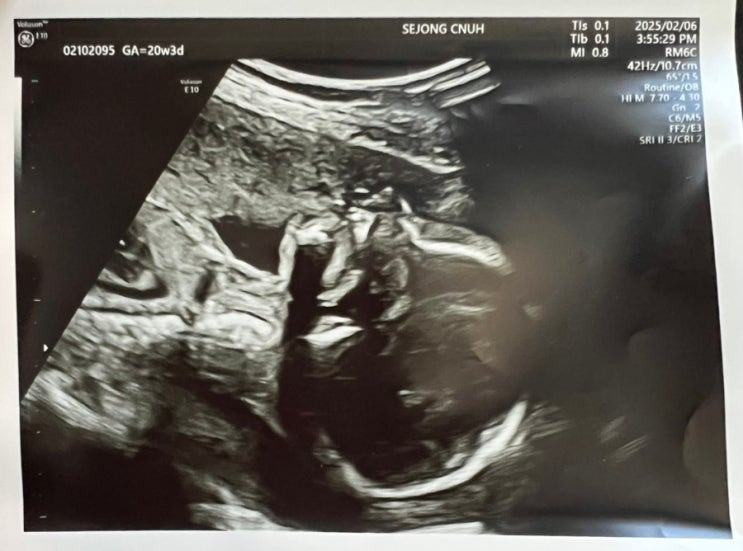

[세종충대병원] 20주 정밀초음파 검사, 24주 임신성 당뇨 검사 예약

안녕하세요. 토디맘입니다:D 2025년 2월 6일 20주차 3일 오늘은 세종충대병원에 정밀초음파검사하러 다녀...